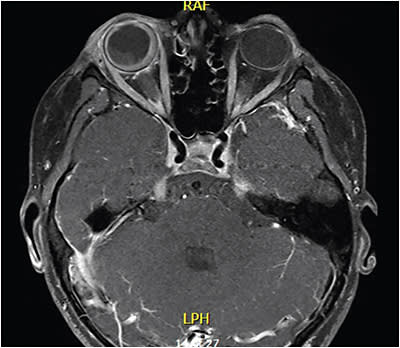

Flow cytometry revealed CD45, CD34, CD10, and CD20 positivity, along with abnormal B-cell population. MRI of the orbits revealed diffuse choroidal/subretinal involvement and likely extension along the right optic nerve sheath, along with protrusion and enhancement of the left optic disc (Figure 3). Given the optic nerve findings, radiation oncology was consulted for evaluation and initiation of emergent radiotherapy.